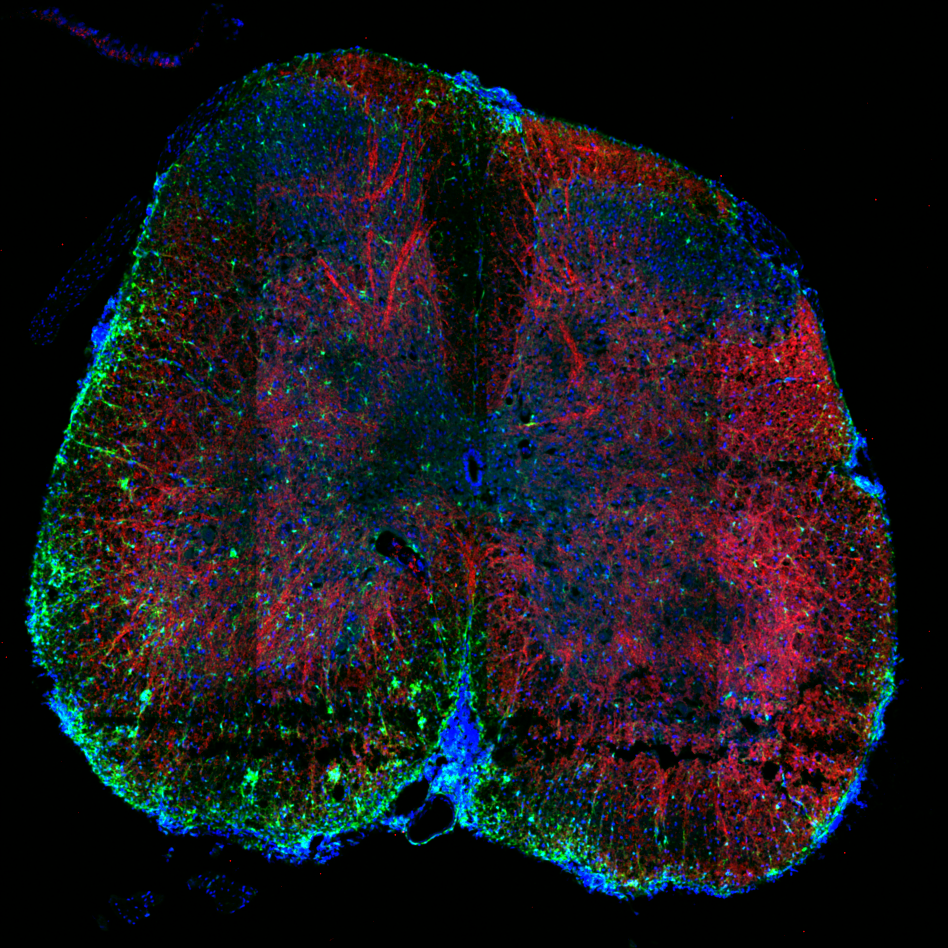

Médula inflamada

Crédito: Antonella Danatro, Laboratorio de Inmunoregulación e Inflamación, Institut Pasteur de Montevideo.

La imagen que se ve aquí corresponde a un corte de médula espinal de un modelo de ratón que no tiene la proteína Torid. Bajo el microscopio se distinguen en rojo las zonas inflamadas, en azul los núcleos de las células y en verde las microglías, que son células del sistema nervioso encargadas de protegerlo de agresiones. La imagen revela que sin la presencia de Torid, la inflamación se desborda, causando una enfermedad neurológica autoinmune grave.